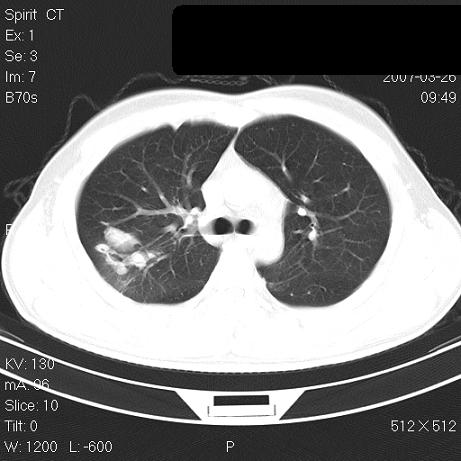

标题: CT7171B:补充治疗后2周复查 [打印本页]

标题: CT7171B:补充治疗后2周复查

治疗后2周复查,请讨论

结合以前的ct片,还是考虑肺挫伤,吸收多了。

支持:创伤性湿肺。现肺挫裂伤(出血 积气)大部分吸收。建议继续治疗!

结合以前的ct片,支持创伤性湿肺。现大部分吸收。

支持:创伤性湿肺、肺挫裂伤。现肺挫裂伤(出血、渗出、液气腔)大部分吸收。建议继续治疗!

支持:创伤性湿肺、肺挫裂伤。现肺挫裂伤(出血、渗出、液气腔)大部分吸收.

经治疗后病灶明显吸收,考虑创伤性湿肺、肺挫裂伤